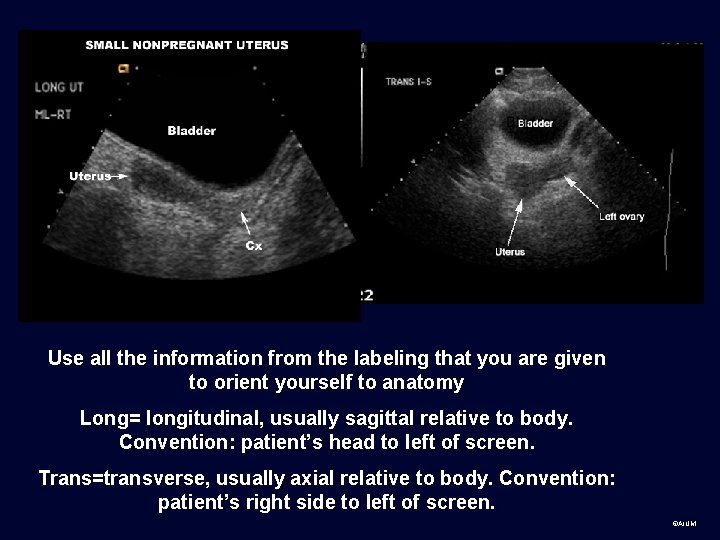

Use all the information from the labeling that you are given to orient yourself to anatomy Long= longitudinal, usually sagittal relative to body. Convention: patient’s head to left of screen. Trans=transverse, usually axial relative to body. Convention: patient’s right side to left of screen. ©AIUM